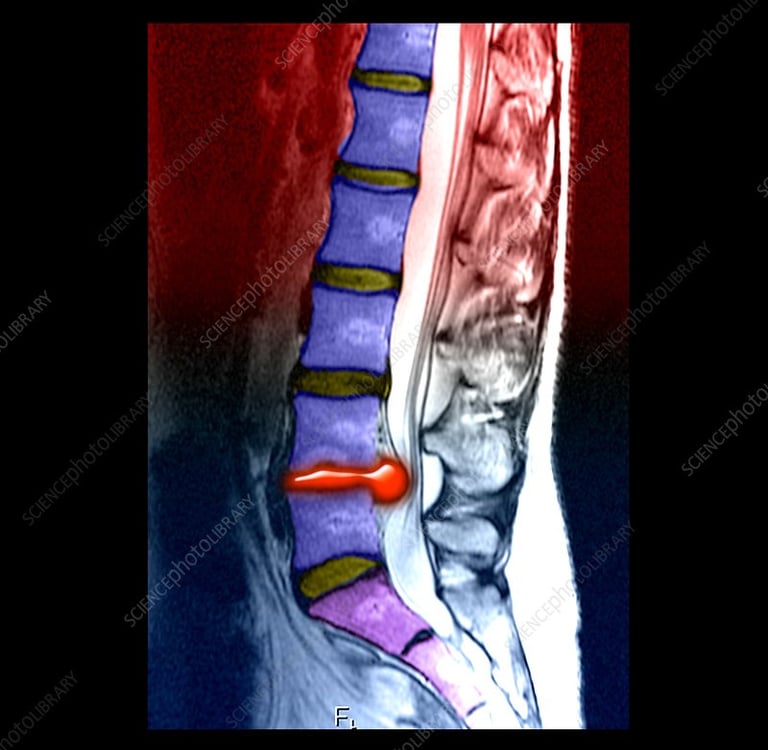

Chiropractic care has become an increasingly popular treatment option for individuals suffering from disc herniations. A herniated disc occurs when the soft inner portion of a spinal disc bulges out through a tear in the outer layer, often compressing nearby nerves and causing pain, numbness, or weakness. Chiropractors are trained to assess spinal misalignments and nerve interference, offering non-invasive solutions that can reduce discomfort and improve mobility. According to Harvard Health Publishing, chiropractic adjustments can relieve musculoskeletal pain, including that caused by herniated discs, by improving spinal alignment and reducing pressure on nerves ("Chiropractic Care for Pain Relief").

One common chiropractic technique used to treat disc herniations is spinal manipulation. This involves carefully controlled movements to restore normal motion to the spine and reduce nerve compression. For example, the Activator Method uses a small handheld device to deliver gentle, targeted impulses to the spine, which may be less likely to aggravate herniated disc symptoms compared to traditional manual adjustments ("Activator Method Chiropractic Technique"). Chiropractors may also employ flexion-distraction techniques, which use a specialized table to stretch and decompress the spine, allowing the herniated material to retract and relieve nerve pressure. These treatments are often considered safer and less invasive than surgical options.